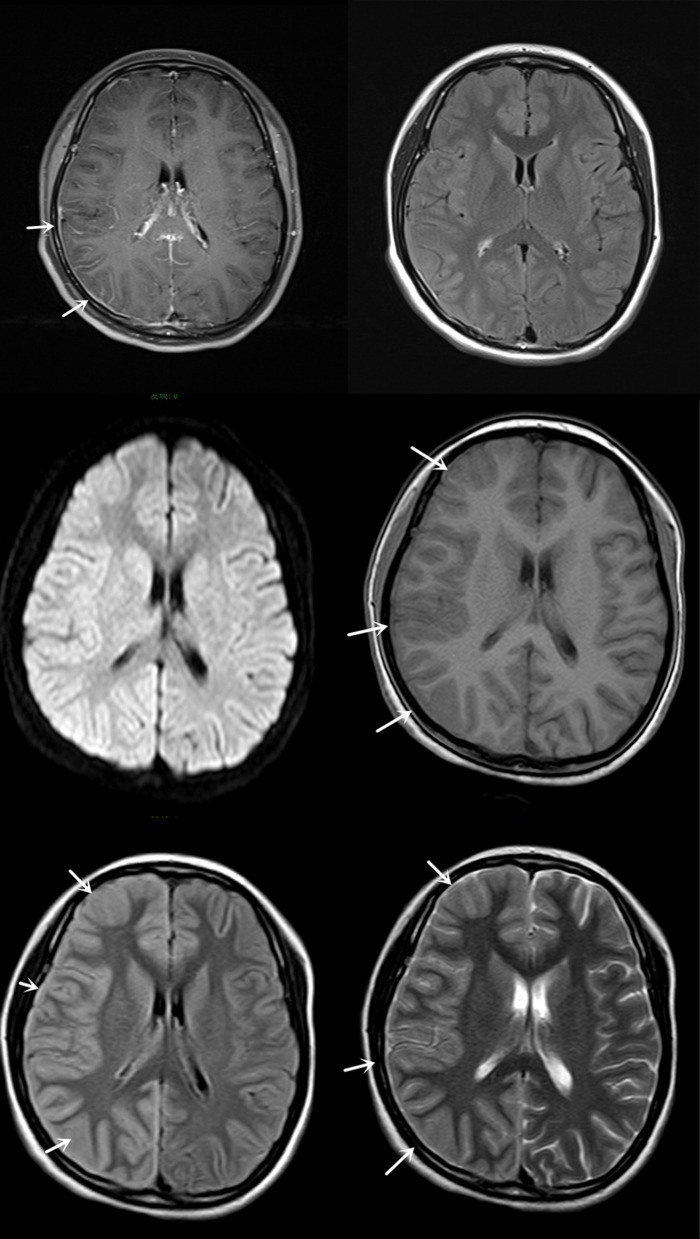

Brief introduction to the disease: The patient developed a right-sided headache a day prior to admission, accompanied by fever, nausea, vomiting, and left-sided limb weakness. On the fourth day, the patient experienced a grand mal epilepsy, marked by unconsciousness, leftward deviation of both eyes, limb convulsions, and foaming at the mouth. Cerebrospinal fluid analysis revealed no apparent abnormalities, Electroencephalography showed abnormal slow waves, imaging studies indicated swelling and meningeal thickening in the right cortex, and genetic testing identified a heterozygous mutation in the ATPIA2 gene. The diagnosis was hemiplegic migraine, and the patient received symptomatic supportive treatment, leading to improvement and subsequent discharge. Flunarizine and sodium valproate were prescribed post-discharge, and the patient achieved complete recovery after a one-month follow-up.